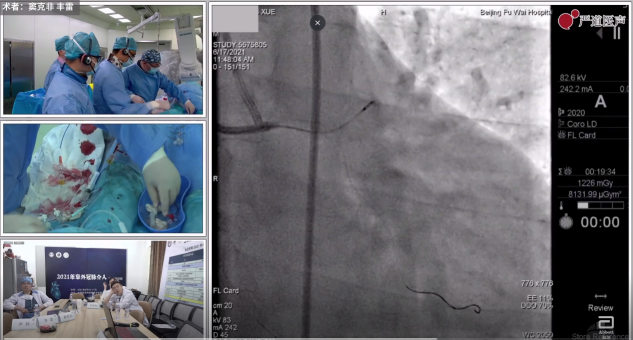

这是培训班手术直播演示环节上窦克非教授、尹栋教授、丰雷教授、朱成刚教授的一部分操作实录。相较于其他医学会议上手术演示环节一开始即通过冠脉造影观摩术者如何运用不同技术将导丝通过病变入口,到达病变远端再植入支架,“2021年阜外冠脉介入基础培训班”更多注重对手术基础操作过程一步一步的拆解和术者手部动作的特写;从穿刺开始,到置管、走导丝、造影、如何选择导管,支架、球囊,并发症的预防以及最后的药物治疗,面面俱到,涵盖冠脉介入手术操作全周期教学。

窦克非教授手术直播花絮

同时,会议室内观看手术直播的专家医师们也会根据术者操作实时点评、讲解术者手术要点和细节,共同分享冠脉介入手术的技巧和经验。值得一提的是,手术虽然是穿插在授课老师的讲课间隙,但手术演示的时机也是随着讲课老师的主题内容有目的、有原因的播放演示,“一个萝卜一个坑”,充分做到了理论与实战的融汇贯通。